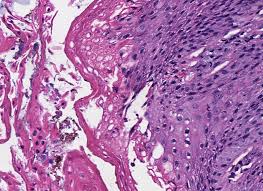

Differential diagnosis between herpes simplex virus (hsv) esophagitis and cytomegalovirus (cmv) esophagitis is challenging because there are many similarities and overlaps between their endoscopic features. Dysphasia and odynophagia are common symptoms with advanced hiv. Esophagitis is the inflammation or irritation of the esophagus. Common forms of esophagitis include reflux esophagitis, infectious esophagitis, pill esophagitis, eosinophilic esophagitis, and radiation and chemoradiation esophagitis. This guide is not intended to be used as a textbook. The results of one survey suggested there may be regional variation, with a. Virtual international pathology institute (vipi). Candida esophagitis (see the image below) is the most common type of infectious esophagitis.

Although hsv esophagitis is much more common in immunosuppressed individuals, it can occur in healthy persons. This guide is not intended to be used as a textbook. Densely matted pseudohyphae and budding spores in squamous debris, fibrinopurulent exudate or necrotic debris. Common forms of esophagitis include reflux esophagitis, infectious esophagitis, pill esophagitis, eosinophilic esophagitis, and radiation and chemoradiation esophagitis. Esophagitis due to herpes simplex virus (hsv) infection1,2.

Although hsv esophagitis is much more common in immunosuppressed individuals, it can occur in healthy persons. Patients typically present with odynophagia, dysphagia, and retrosternal chest pain. We here present a case of hsv esophagitis that was presented with its characteristic features. Differential diagnosis between herpes simplex virus (hsv) esophagitis and cytomegalovirus (cmv) esophagitis is challenging because there are many similarities and overlaps between their endoscopic features. Esophagitis due to herpes simplex virus (hsv) infection1,2. Less common causes of esophagitis and esophageal injuryand esophageal anatomic anomaliesseptember 16, 2009. This form of esophagitis typically occurs when. Herpes esophagitis is a viral infection of the esophagus caused by herpes simplex virus (hsv). Alimentary tract pathology in infants and children. Eosinophilic esophagitis title pathology reviewptyp loattrfree full text sb. Densely matted pseudohyphae and budding spores in squamous debris, fibrinopurulent exudate or necrotic debris. Common forms of esophagitis include reflux esophagitis, infectious esophagitis, pill esophagitis, eosinophilic esophagitis, and radiation and chemoradiation esophagitis. Causes of esophagitis include stomach acids backing up into the esophagus, infection, oral medications and allergies.